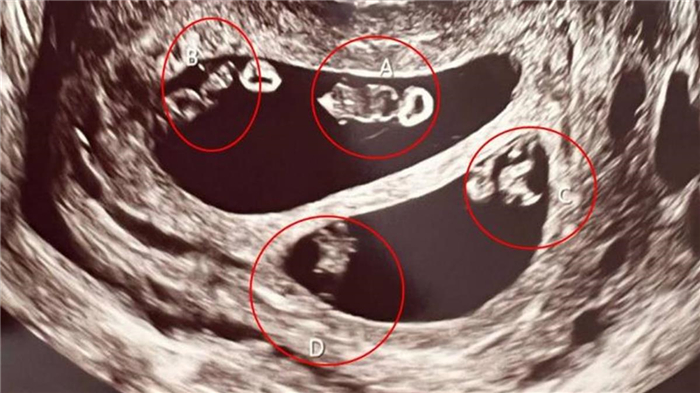

根据《每日邮报》 (Daily Mail) ,一名住在美国麻州的35岁女子内斯 (Ashley Ness) ,与47岁的男友瓦尔 (Val) 始终没有孩子,好不容易怀孕,前往医院检查,竟发现肚子有2对同卵双胞胎,总共2男2女,与四胞胎不同,这样的情形在医学上,只有7千万分之1,让她当场吓傻。

内斯提到,当医生看到超音波时,也感到很困惑,还在上方标记A跟B,想清点胎儿人数,自己忍不住询问“是不是怀了双胞胎”,但医生却没有回答,仅说必须离开一下,方便确认目前状况,没想到回来后,就宣布了一个不可思议的消息。